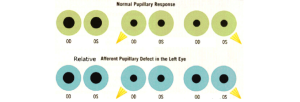

Pupillary response

The pupillary light reflex is easily tested and can help with localizing the cause of the coma. To perform this test, first, observe the pupil size in ambient and dim lighting for anisocoria. Shine a bright light into one eye and then alternate between each eye, observing both pupils for any reactivity. Note if the pupils react briskly, sluggishly, or have no response. Swinging the flash light from one eye to the other can detect a relative afferent pupillary defect.

A normal pupil examination includes equal sized (i.e., isocoric) pupils in light and dark illumination; normal direct and consensual pupillary constriction to light stimulus; round and regular pupils; an intact near stimulus (requires voluntary effort), and the absence of a RAPD.